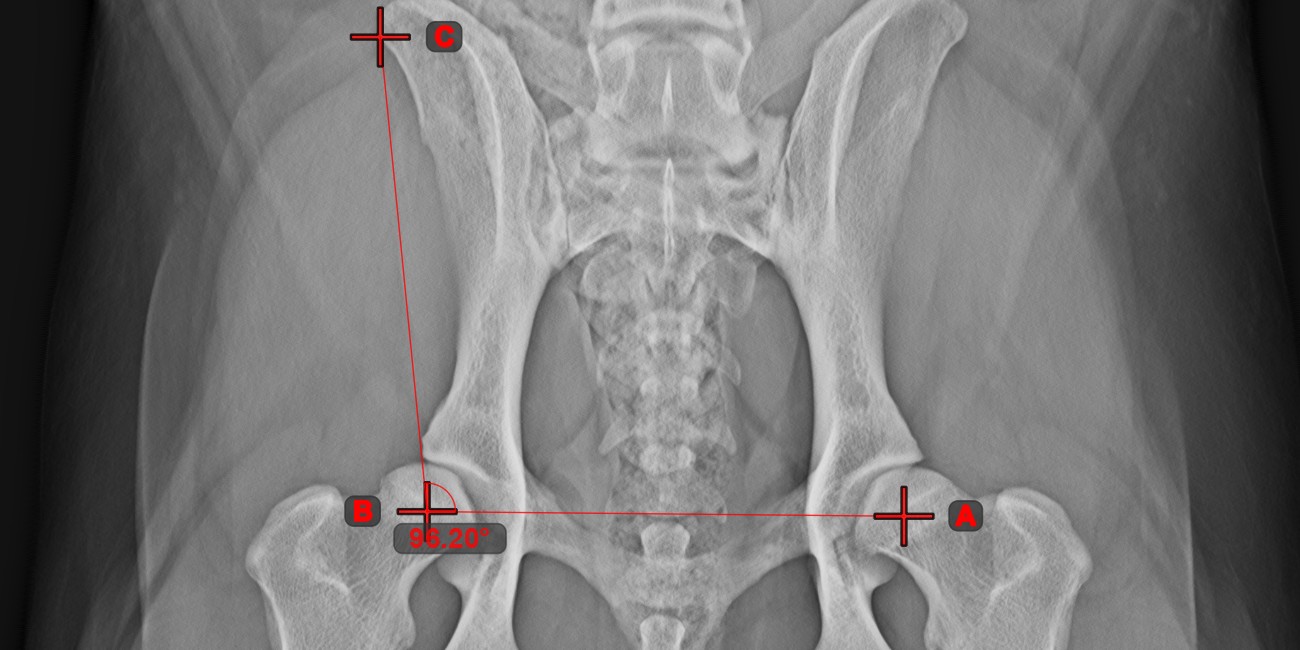

Angle from 3 Points¶

The Angle from 3 Points tool is a simple and effective way to calculate an angle from just three points.

Start by selecting the tool from the left toolbar and assign it to one of the available mouse buttons. Place the start point of the initial side, the vertex, and the end point of the terminal side of the angle, or select the points from the scene. The sides of the angle will be automatically constructed, thus calculating the angle between the lines.

Modify the position of the three points to change the arc of the angle by using the Select/Move Item tool.